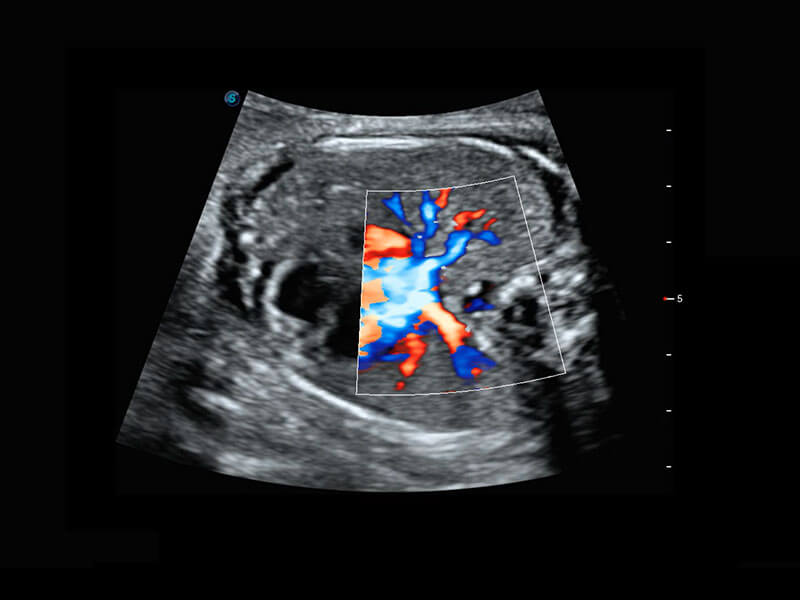

P60搭载宽频带线阵探头、宽景成像、弹性成像技术,为您提供乳腺应用方案。P60支持高频相控阵探头、线阵探头、腹部高频探头、腹部微凸探头等,丰富的探头群搭载敏感的彩色血流成像,适用于新生儿多种脏器检测要求,满足新生儿筛查需求。

新生儿肝血管癌